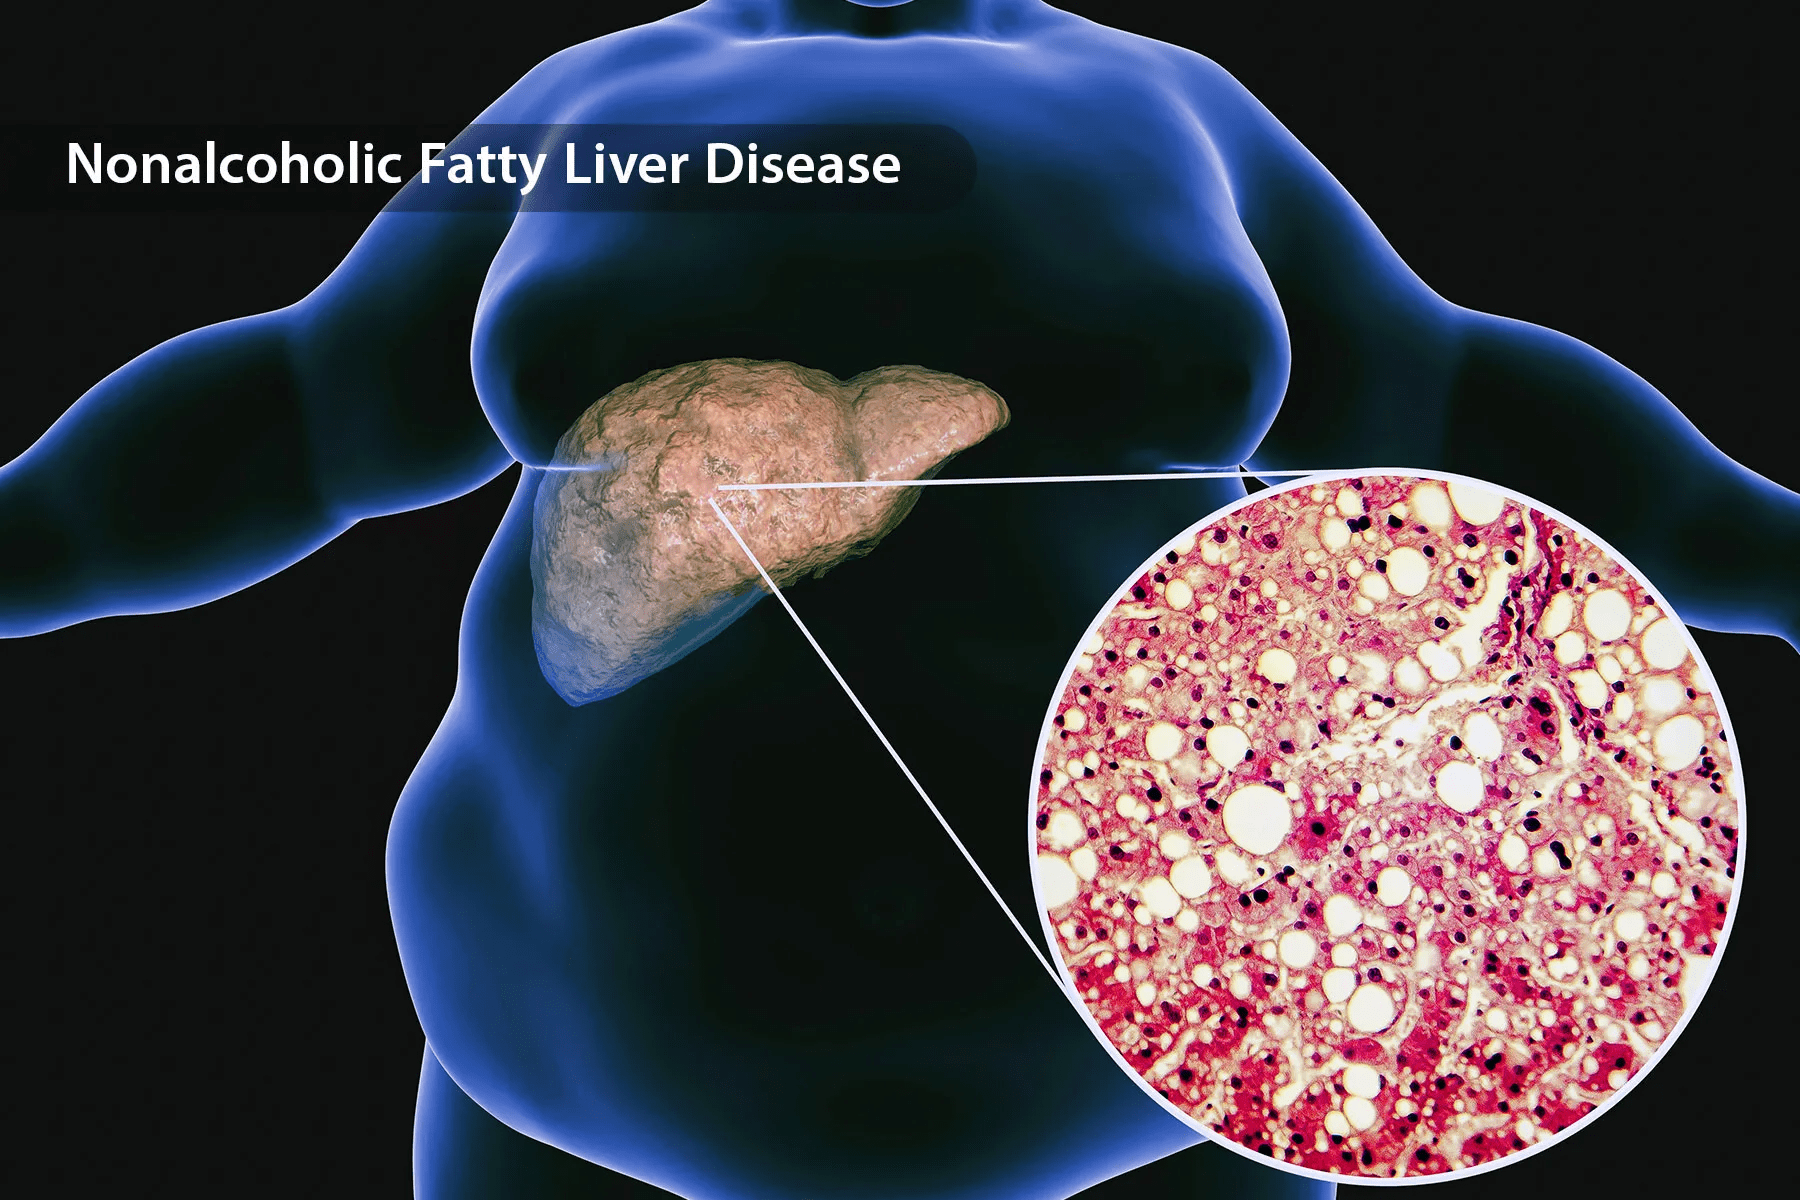

Fatty liver disease is often called the “silent epidemic.” It doesn’t hurt, it doesn’t warn you, and most people don’t find out until it’s already well developed. Over one in four adults in the U.S. has it—many of them believing they eat “clean.” So, what’s the hidden trigger?

When you eat or drink something high in fructose (the sugar in fruit juice, soda, or processed foods), your liver becomes the main processing center. Unlike glucose, which muscles can use for fuel, fructose must be metabolized entirely by the liver. When there’s too much of it, your liver starts turning that excess into fat. Over time, this fat builds up and leads to non-alcoholic fatty liver disease (NAFLD)—a condition now seen in both adults and teenagers.

And here’s the twist: you don’t need to be overweight to have it. Even thin individuals can develop fatty liver if their diet is loaded with sugary “health” foods.

Studies suggest that by the time most people are diagnosed, fat already covers more than 5–10% of their liver. At that stage, the organ’s ability to detoxify and balance hormones is compromised. And if left unchecked, it can progress to inflammation, scarring, or even cirrhosis.